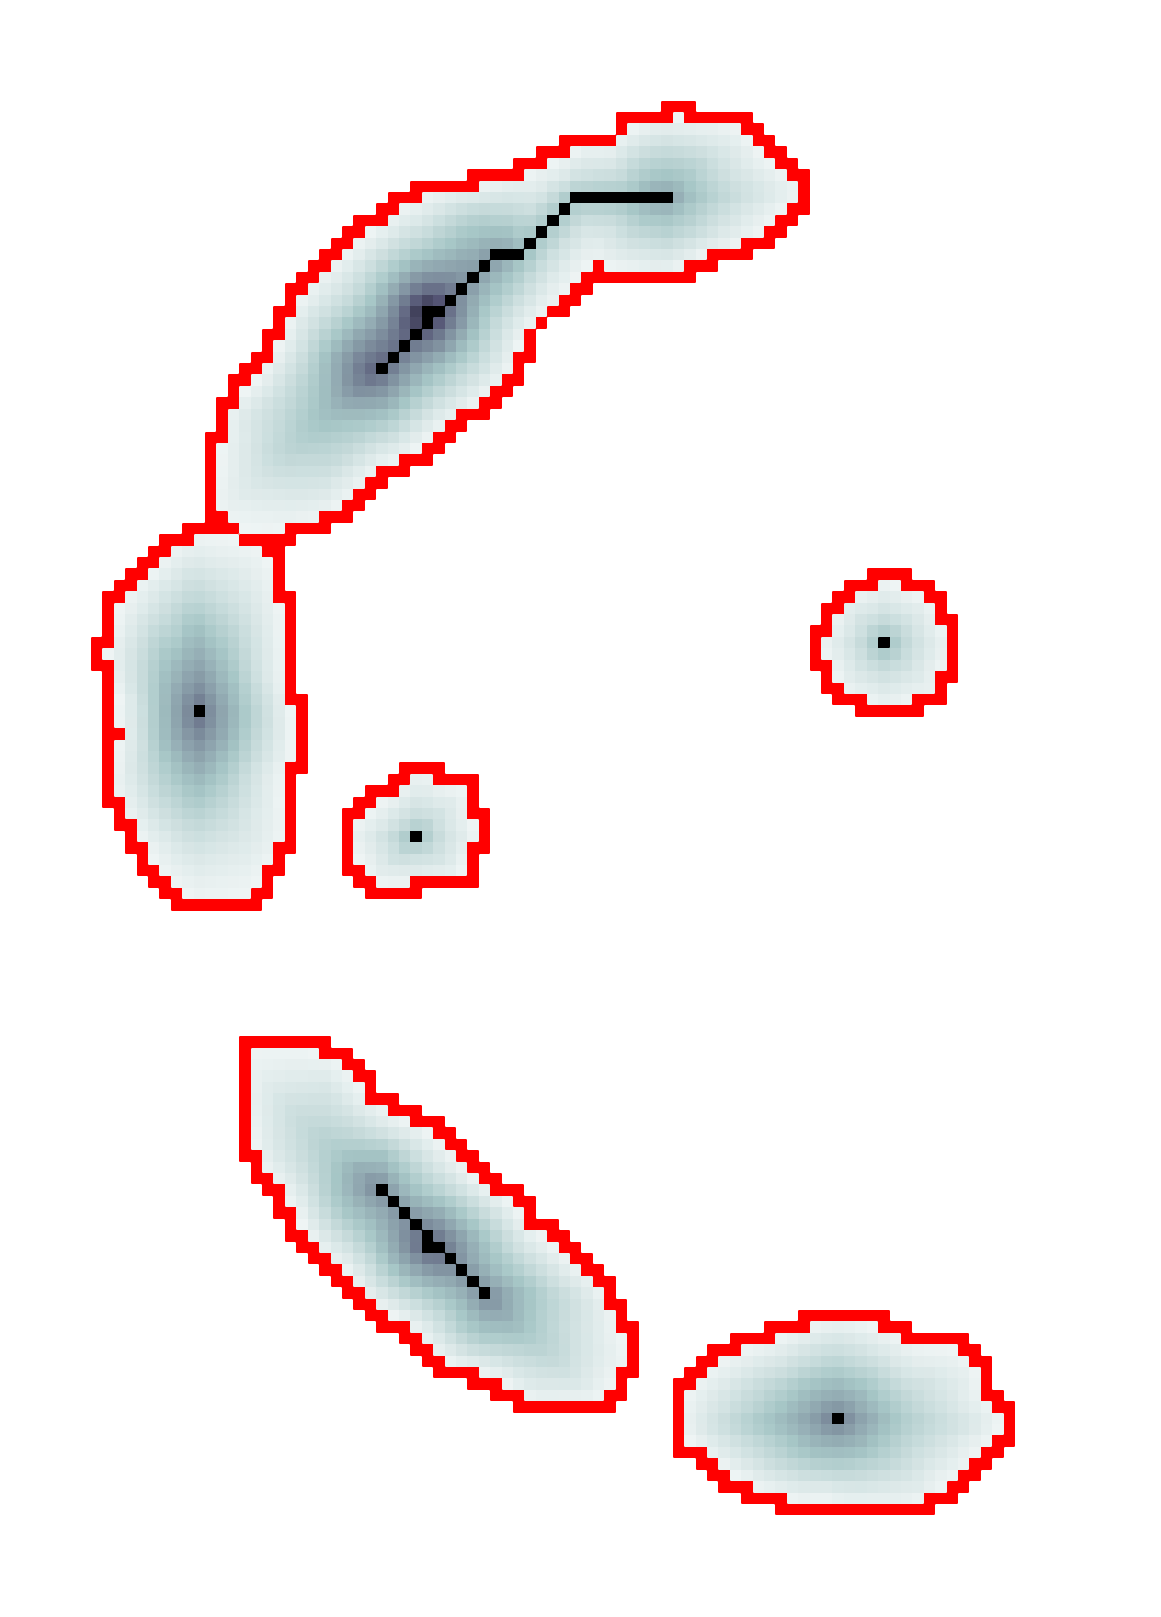

3.2 Connected Geodesic Paths as Vascular Tree

Representative examples of degraded synthetic images from SVT and the respective GT are shown in fig. 4 together with the connected graphs extracted by VTrails. Analogously, the same set of images are reported for the real images TOF and CTA in fig. 4. Qualitatively, the extracted set of connected geodesic paths shows remarkable matching with the provided GT in all cases. First, we verify the acyclic nature of the graph. We found no cycles, degenerate graphs and unconnected nodes, meaning that the extracted connected geodesic paths represent a connected geodesic tree. Precision and recall are then evaluated for the identified branches. Also, error distances are determined as the connected tree’s binary distance map evaluated at GT. Average errors () precision and recall are reported (meanSD) in table 1. Note that no pruning of any spurious branches is performed in the analysis.